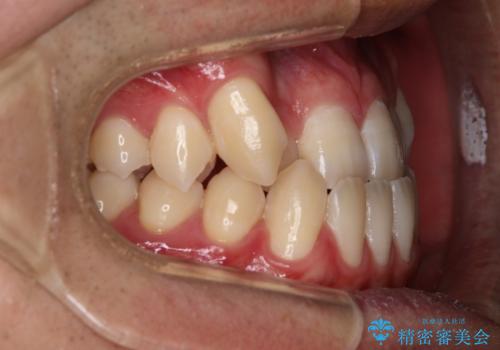

- 前歯の歯並びと噛み合わせを主訴に来院されました。

左右の噛み合わせが反対咬合であることと下顎の皮質骨が薄いため治療計画をしっかりと立てて行う必要のあるケースでした。